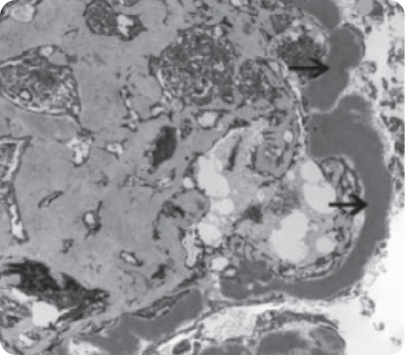

Электронная микроскопия6

Image

Электронная микроскопия

• Необходима в 21% случаев для корректной оценки биопсийного материала.

• Диагностика ряда заболеваний невозможна без проведения электронной микроскопии: синдром Альпорта, болезнь тонких базальных мембран, коллагено-фибротическая гломерулопатия, фибриллярный и иммунотактоидный гломерулонефрит8, 9.

• Предоставляет дополнительную информацию к морфологическому диагнозу в 24% случаев, включая тубуло-ретикулярные формации, характер организованных структур при криоглобулинемии и амилоидозе8, 9.